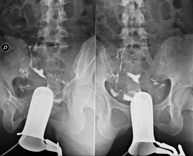

Prova diagnòstica que consisteix en obtenir imatges radiològiques de l'intestí gros (còlon i recte) mitjançant l'ús de raigs X. S'utilitza un contrast opac que s'administra a través del recte en forma d'ènema i també s'introdueix aire per expandir el còlon.

La urografia intravenosa (UIV) consisteix en l'obtenció d'imatges radiològiques seriades del ronyó, vies urinàries i bufeta. Aquest estudi requereix sempre l'ús d'un contrast iodat. - Cistografía (CUMS)

La cistouerotrografia miccional seriada consisteix en l'obtenció d'imatges radiològiques per valorar l'anatomia i la funció de la uretra i la bufeta amb l'administració de contrast iodat a través d'una sonda vesical. - Uretrocistografia (Uretro-Cums)

La uretrocistrografia retrògrada i miccional consisteix en l'obtenció d'imatges radiològiques per valorar l'anatomia i la funció de la bufeta i de la uretra. S'aplica material de contrast a través d'una petita sonda que es troba a la uretra i s'obtenen imatges durant l'ompliment i el buidatge de la bufeta. - Pielografia ascendent per catèter

Estudi que utilitza els raigs X per obtenir una imatge dels ossos de maluc i descartar luxacions. - Cistografia

La cistouretrografia miccional seriada consisteix en l'obtenció d'imatges radiològiques per valorar l'anatomia i la funció de la uretra i la bufeta amb l'administració de contrast iodat a través d'una sonda vesical.